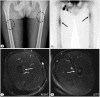

(A) Anteroposterior (AP) X-ray of both femurs displays subtle cortical thickening in the medial aspects of the subtrochanteric area bilaterally. A synchronous thin radiolucent line is also depicted coursing within the thickened cortexes, thus indicating a non-displaced fracture (black dashed oval). (B) Subsequent bone scintigraphy illustrates abnormally increased radiotracer uptake in the aforementioned areas (black arrows). No other regions with pathologic uptake were demonstrated. Axial T2-weighted fat-saturated images of the (C) right and (D) left femurs similarly revealed mild cortical thickening localized in the medial facets of the subtrochanteric area of the femur, with concomitant mild signal hyperintensity also being illustrated due to bone marrow oedema because of the bilateral fractures (white arrows).